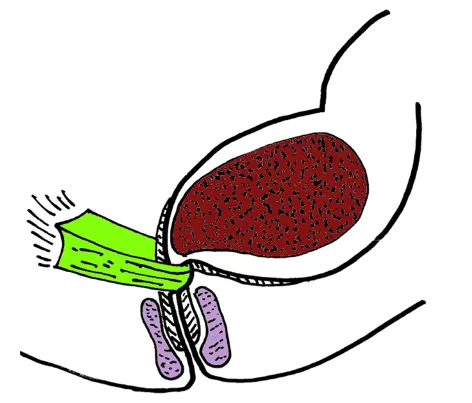

اختلالات عصبی که باعث بیماری هایی مانند پارکینسون، MS، دیابت یا آسیب به اعصاب کنترل کننده روده می شوند نیز می توانند باعث رفلاکس مدفوع شوند. اختلال عملکرد اسفنکتر مقعدی، جراحی های قبلی یا آسیبهای لگنی، رژیم غذایی فاقد فیبر و کم تحرکی نیز ممکن است در بروز رفلاکس مدفوع نقش داشته باشد.

در بیماران مبتلا به اختلال عملکرد عضلات کف لگن یا اسفنکتر مقعدی از بیوفیدبک تراپی یا حتی جراحی برای اصلاح مشکلات ساختاری استفاده می شود. درمان آنتی بیوتیکی موقت نیز برای تغییر فلور روده می تواند به درمان این بیماری کمک کند.